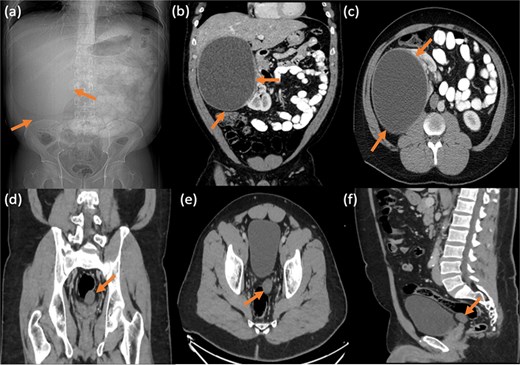

Ultrasound showed a large cystic lesion in the right kidney with internal debris and fluid–fluid levels (Fig. 1). Contrast-enhanced CT confirmed a thick-walled, fluid-filled cyst in the right upper renal pole without septations or calcifications—consistent with recurrent hydatid disease (Fig. 2). Incidentally, a small pelvic cystic lesion was seen adjacent to the rectum and seminal vesicle.

Frontal abdominal radiograph in supine position showing opacity occupying the right upper abdominal region with paucity of bowel loops (a). Followed by contrast enhanced CT abdomen and pelvis with reconstructed images showing a large thick walled non-septated non-calcific right renal cortical cyst (b and c). No right perinephric/pericystic fat stranding or free fluid, preserved tissue planes with surrounding related organs. Incidentally noted small similar looking cystic lesion in the left pelvic region, inseparable from the rectal wall and left seminal vesicle showing no gross fat or calcification (d–f).